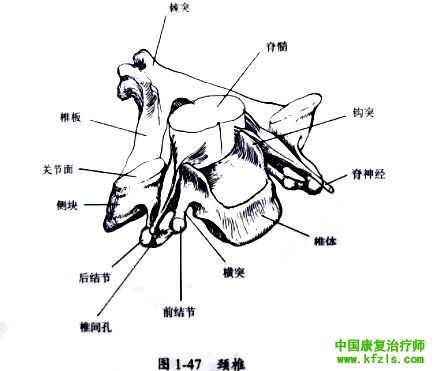

颈椎钩突为C3~C7椎体上部两侧向上的嵴状突起。钩突增加椎体的稳定性,并构成椎间孔的前内侧界(图1-47)。钩突骨质增生时可累及椎间孔,直接压迫神经根或限制神经根的活动(图1-48)。

在颈椎的斜位片上可以更好地判断椎间孔和钩突累及情况(图1-49)。

需注意,神经根可出现在脊髓和椎体的45°角上, 同样的角度也存在于椎间孔和椎体之间。钩突的骨质增生除非产生症状,否则并无重要的临床意义。